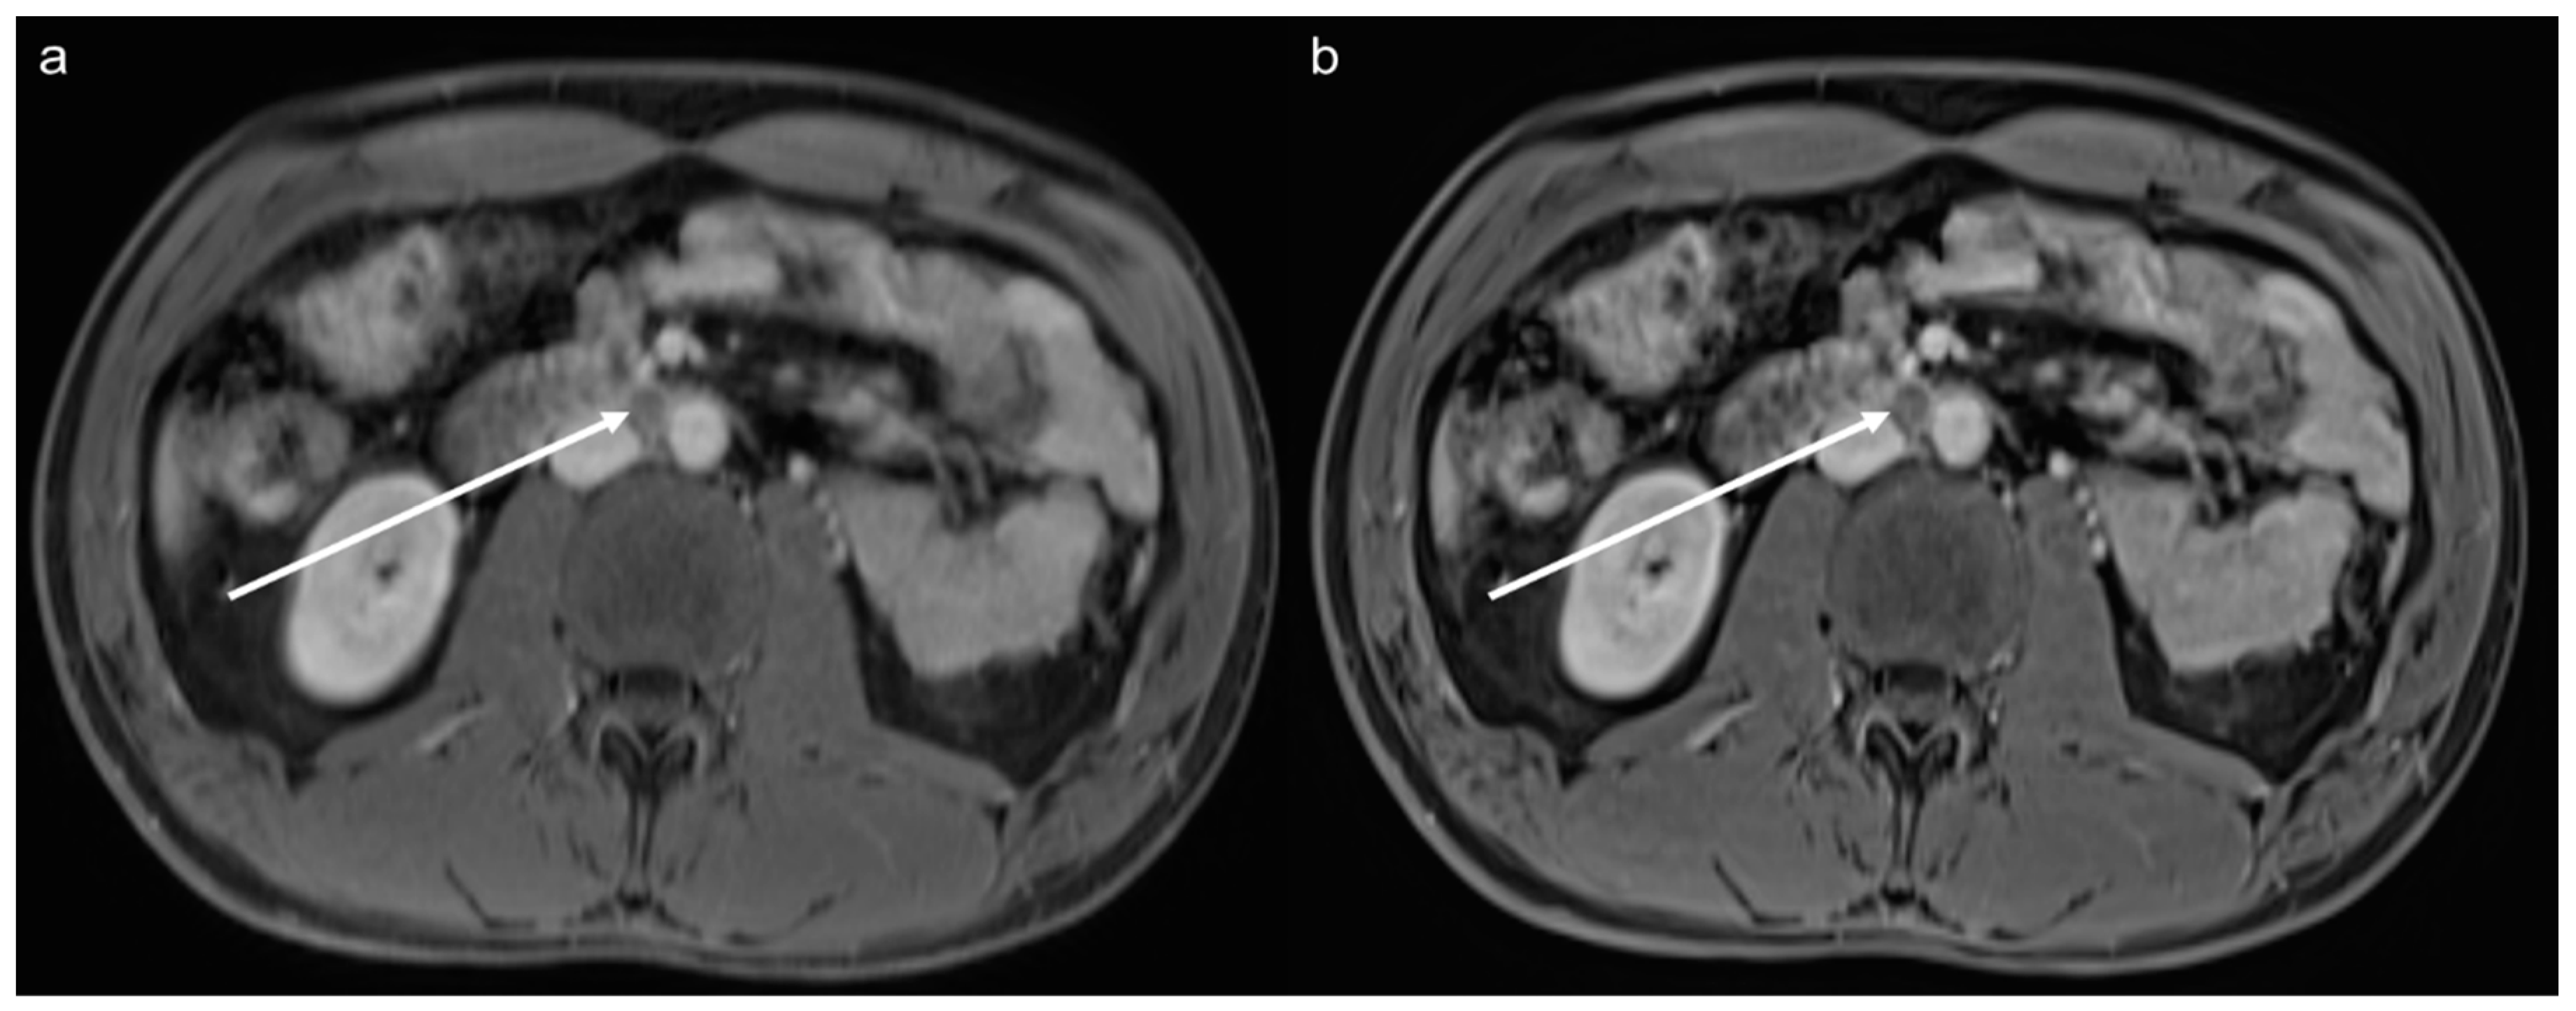

3.3. Qualitative Results of the Precontrast Images

3.4. Qualitative Results of the Postcontrast Images

3.5. Lesion Assessment